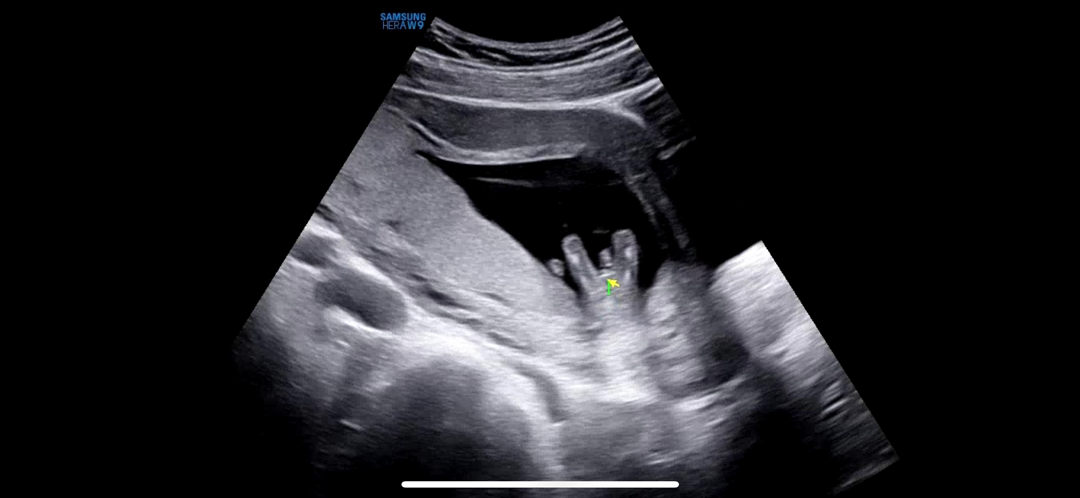

12주 6일차 성별 질문드려요!

다리 사이에 이렇게 보이는데 확실한 아들일까요.??